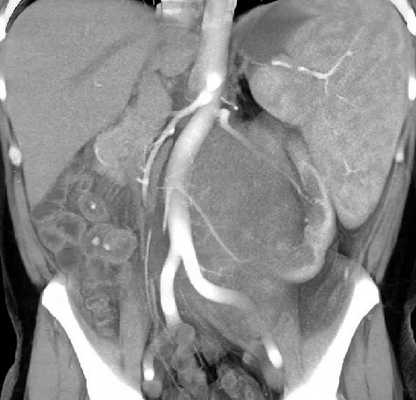

![3D-реконструкции опухоли Вильмса]()

3D-реконструкции опухоли Вильмса пациентов детского отделения НМИЦ онкологии им. Н.Н. Петрова